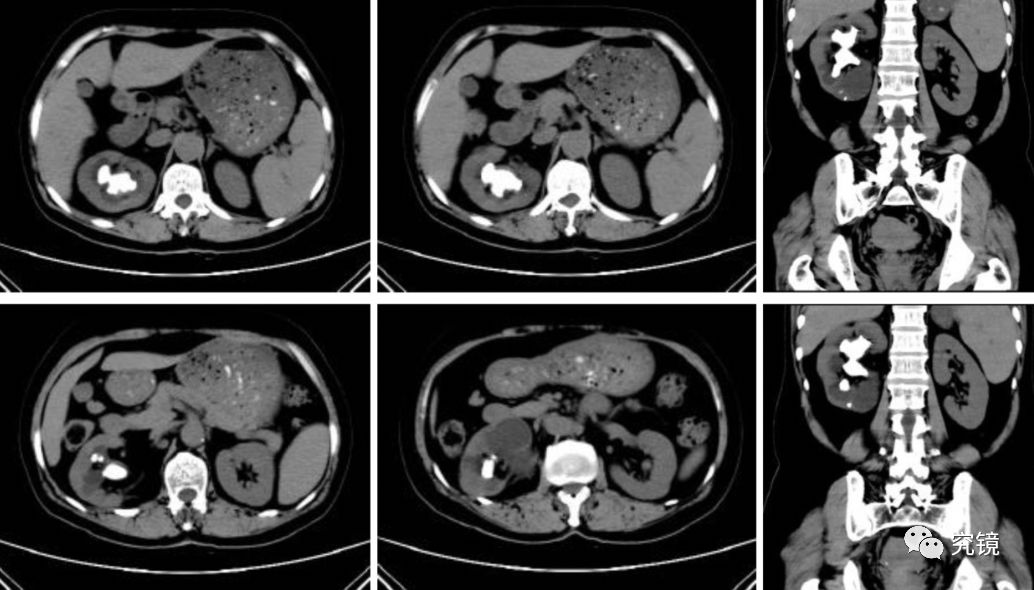

ct影像显示肾脏被巨大结石霸占.长沙晚报通讯员 胡薇华 陈昊 供图

ct影像显示巨大肾结石(红圈内)

图1.ct提示右肾多发铸型结石

(ct及ctu显示左肾铸型结石)03核磁共振(mru)检查核磁共振(mru)检查无